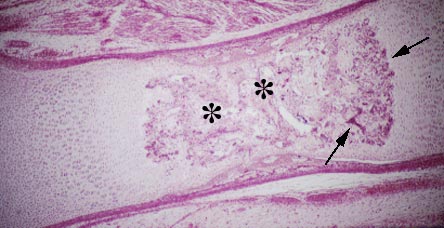

IV-31A Endochondral ossification. Cartilage erosion (*) is seen in shaft of bone along with bone deposition (arrows). Cartilagenous epiphyses are seen at both ends of this long bone.